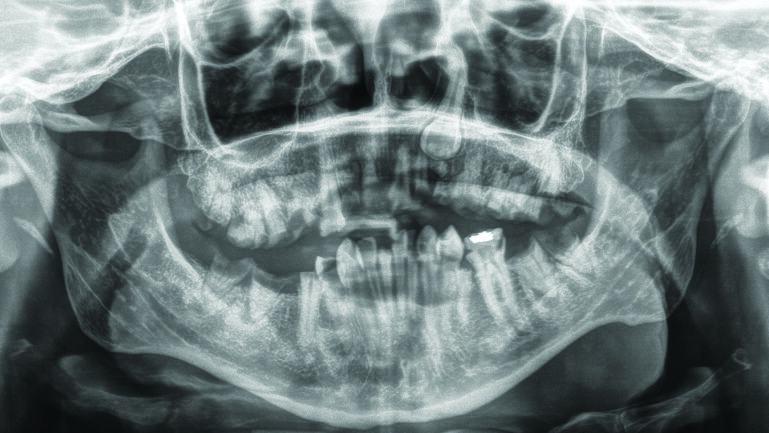

Davis pan1 alternate text for this image

Abstract Tetanus is a serious, life threatening infection caused by the bacterium, Clostridium tetani. Due to almost widespread vaccination against tetanus toxoid the incidence in the developed world is extremely low. Vaccination in childhood does not result in lifelong immunity and requires “booster” doses of the vaccination every ten years. In the United States, the … Read more